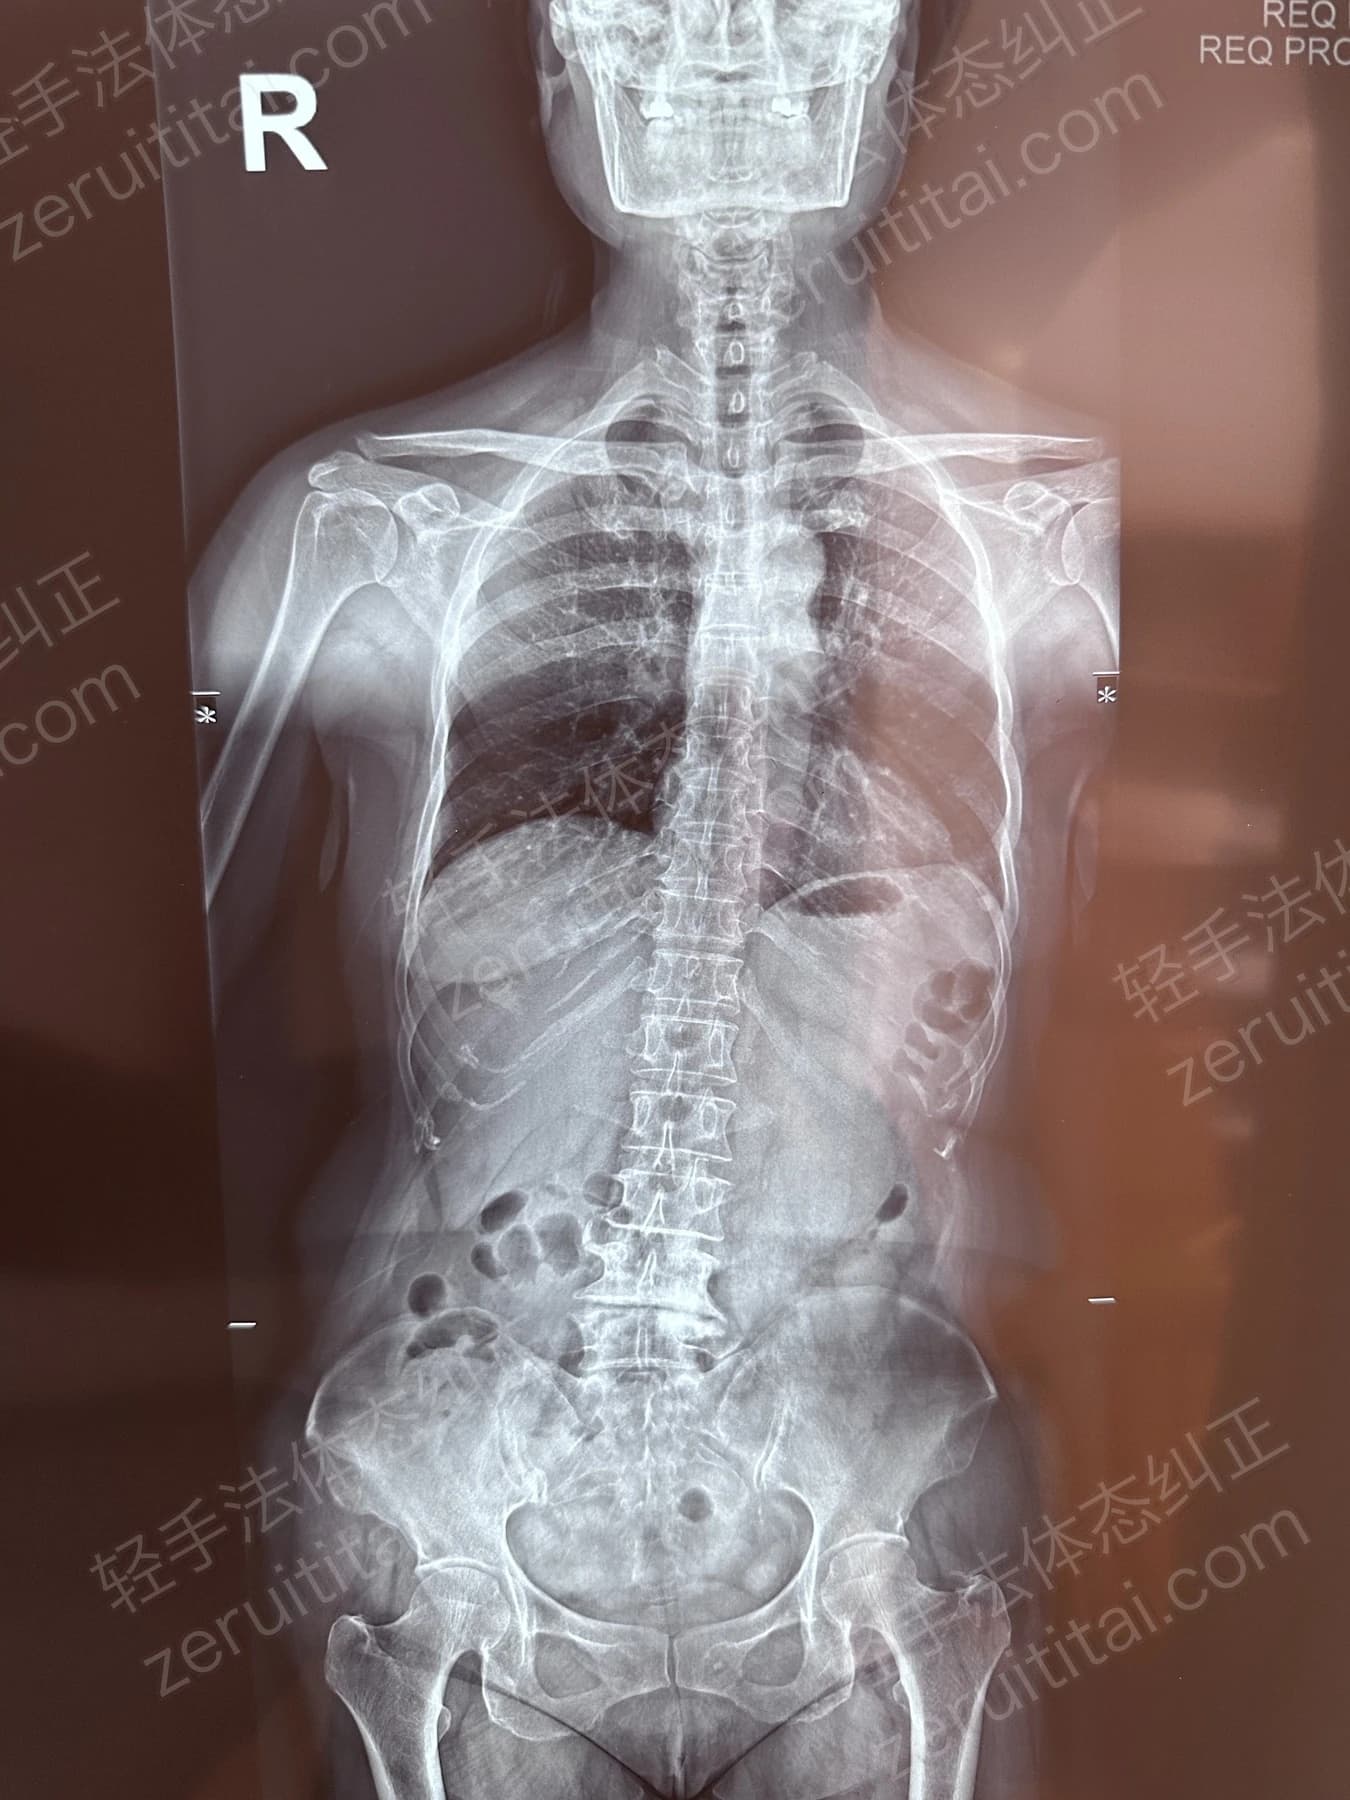

2023.05.30

第 4 次记录